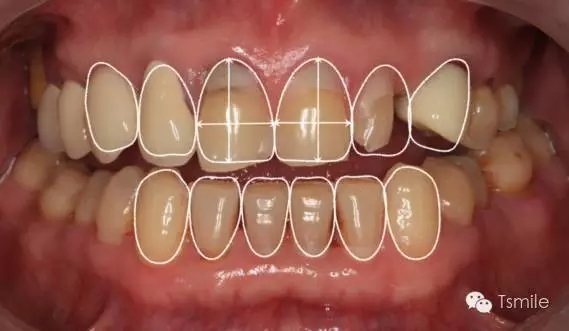

美學(xué)表達(dá)就是要把醫(yī)師大腦中形成的美學(xué)設(shè)計(jì)思想,采用各種方法準(zhǔn)確、真實(shí)、直觀地表達(dá)給患者,進(jìn)行醫(yī)患溝通,進(jìn)行口內(nèi)診斷性美學(xué)修復(fù)。在口內(nèi)根據(jù)患者主客觀反應(yīng)進(jìn)行調(diào)改,形成最終的美學(xué)修復(fù)設(shè)計(jì)。最后進(jìn)行醫(yī)技溝通,指導(dǎo)技師完成修復(fù)體制作。美學(xué)表達(dá)的方法有:數(shù)碼圖像設(shè)計(jì)(如DSD)、診斷飾面(Mock-up)、診斷蠟型(Wax-up)、模型外科、臨時(shí)修復(fù)體等。

例如面對(duì)一個(gè)牙列重度磨耗的美學(xué)修復(fù)患者,我們首先根據(jù)患者主訴和美學(xué)檢查形成美學(xué)設(shè)計(jì),然后通過數(shù)碼圖像表達(dá)美學(xué)設(shè)計(jì)思想,制作診斷蠟型,口內(nèi)制作診斷飾面,更加真實(shí)地表達(dá)美學(xué)設(shè)計(jì)。根據(jù)患者的要求和口內(nèi)試戴情況調(diào)改診斷飾面,最終確定美學(xué)修復(fù)設(shè)計(jì),即最終修復(fù)體的各種美學(xué)參數(shù)。接下來就是美學(xué)實(shí)現(xiàn)過程,在診斷飾面上進(jìn)行精確地牙體預(yù)備,制取印模和工作模型,技師按照最終診斷飾面的形態(tài)、大小和排列制作最終美學(xué)修復(fù)體,最后完成修復(fù)體粘接。

在前牙的美學(xué)分析中有四個(gè)最重要的美學(xué)影響因素,稱之為前牙美學(xué)四要素。包括上中切牙切緣的位置、上中切牙臨床冠的寬長(zhǎng)比、上中切牙齦緣的位置、上前牙的寬度比例。這四要素是影響前牙美學(xué)的主要因素,根據(jù)這四要素就可以簡(jiǎn)單、快速、準(zhǔn)確地分析患者前牙存在的美學(xué)缺陷。根據(jù)這四因素就可以準(zhǔn)確、直接地進(jìn)行患者前牙的美學(xué)修復(fù)設(shè)計(jì)。